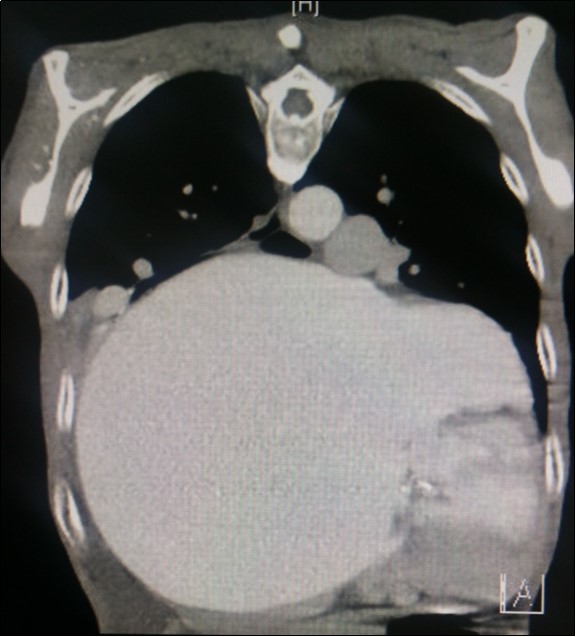

A dramatically dilated left atrium was seen on a TTE (see Figure 2a, Figure 2b, Figure 2c, and Figure 2d). Severe mitral stenosis with associated regurgitation was evident, with a mean gradient across the valve of 11mmHg and a hyperdynamic left ventricle. The left atrial volume measured by Simpson’s biplane method (see Figure 2c) was 2108mL, or 1548.5 ml/m2, based on height 1.55 metres and weight 44 Kg. Normal left atrial volume in a woman is 16 - 34 ml/m21. The computed tomography scan (CT) chest AP view (see Figure 3) is also shown.

Figure 3.Computed tomography scan (CT) chest AP view, showing the extent of the left atrium filling the left and right hemithoraces.